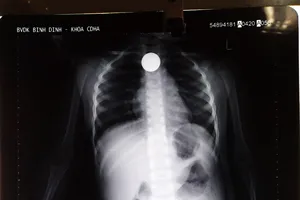

Đồng xu mắc trong thực quản cháu bé 3 tuổi

Y tế - Sức khỏe

25/02/2020 19:59